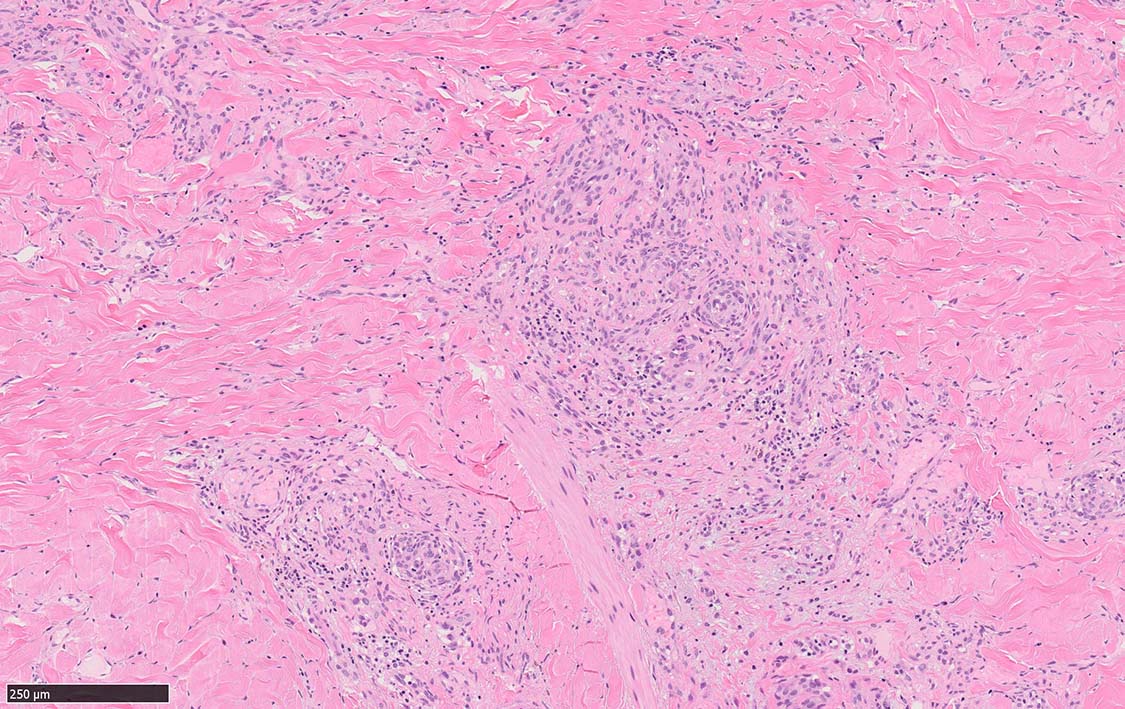

局面状病変の病理

病変は真皮から皮下脂肪織に及ぶようになり, 血管内皮様細胞による新生管腔の増加と拡張, 浮腫が著明になる. 赤血球漏出やヘモジデリン貪食細胞もめだつようになる.

膠原線維間に紡錘形細胞が増生してくる.

結節性病変の形成

紡錘形細胞が著しく増生し束状に走行する部分と, 内皮細胞様細胞による多数の小管腔構造が巣状にひろがり, 一見, 線維腫と血管腫が混在しているように見える. 一部の症例を除き, これらの増生細胞は異型性に乏しいことが多い.

細血管周囲に血管内皮様の紡錘形細胞が増生, 一部に赤血球をいれた裂隙の形成がある. 細胞の異型はみられず, mitosisの増多もない. hemosiderin-laden macrophageが散在する.

病変は真皮内に現局している. 初期斑状病変に相当すると考えられる. 本例では, 特徴とされる形質細胞浸潤増加はみられない.